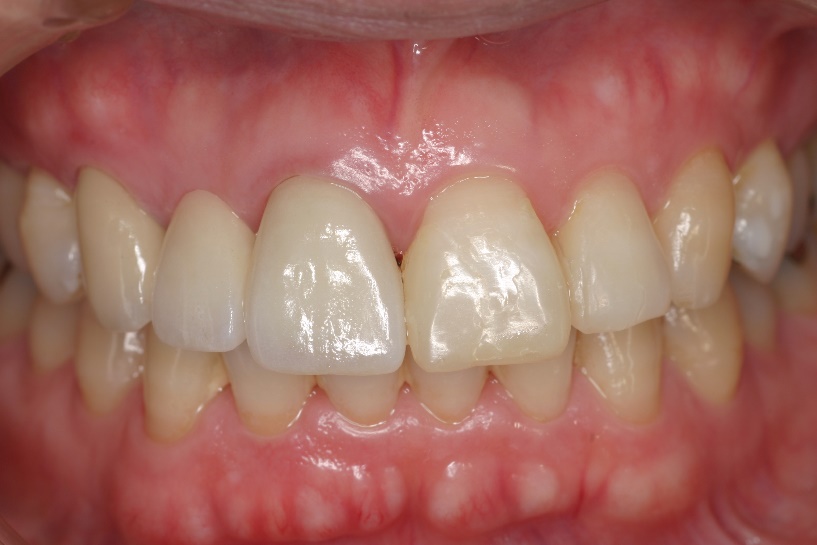

歯肉圧排をしたところ

治療後